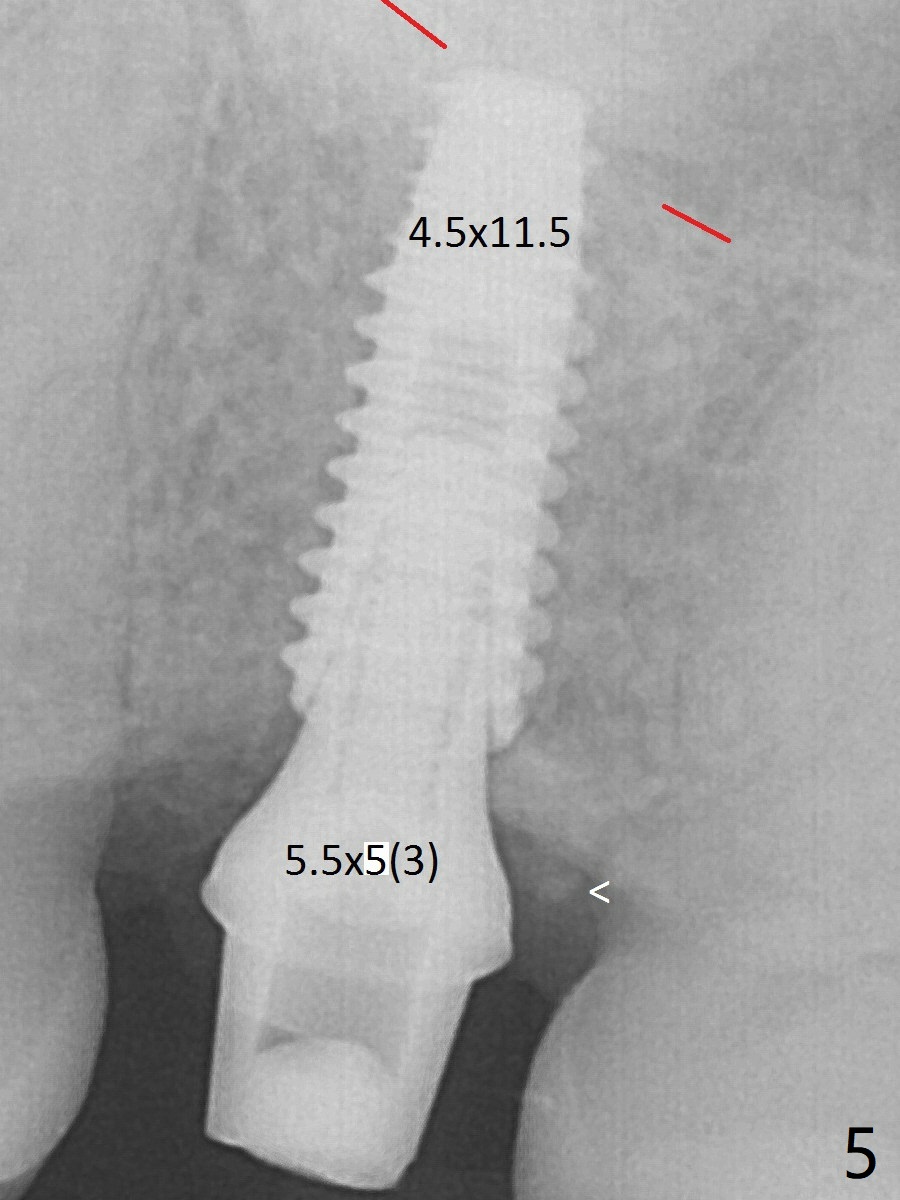

A 3.7 mm drill has to be used for 12 mm before placement of a 4.5x11.5 mm implant with >35 Ncm (Fig.5). A 5.5x5(3) mm abutment is placed with allograft (<) placed around the implant. Following suturing, periodontal dressing is applied around the implant. The abutment dislodges 3 months postop (Fig.6). Crown is delivered 3 weeks later. The abutment screw is retightened ~ 2 months later.